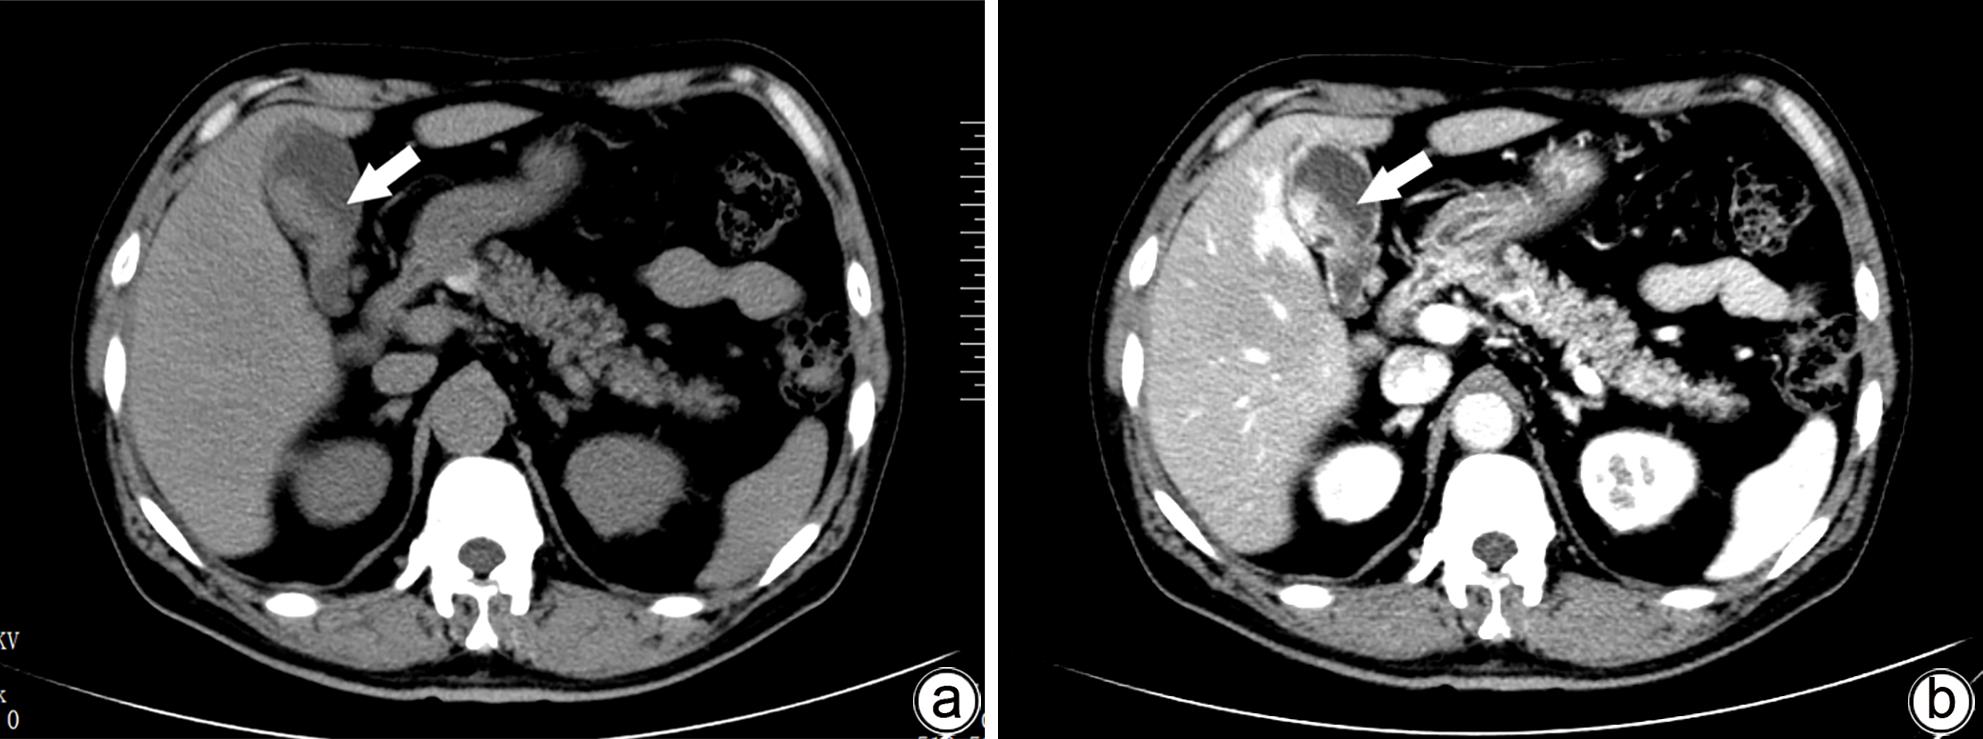

胆囊肉瘤样癌16例临床诊治及预后分析

周雅淑, 马怡晖, 裴家鑫, 孟园园, 郭鹏, 梁曦月, 路太英

2024, 40(4): 767-772. DOI: 10.12449/JCH240420

摘要(1270) HTML (361) PDF (1085KB)(79)

摘要:

目的  分析胆囊肉瘤样癌(GBSC)的临床病理特征、诊疗方法及预后。  方法  回顾性分析2015年1月—2023年4月郑州大学第一附属医院收治的16例胆囊肉瘤样癌患者的临床资料,包括患者的一般资料、临床表现、影像学特点、病理学特点和治疗方式等,并进行随访。采用Kaplan-Meier法进行生存分析,并绘制生存曲线,Log-rank检验比较组间差异。  结果  16例患者中男6例,女10例,年龄(62.9±8.4)岁。主要临床表现为右上腹痛13例(81.3%)、恶心5例(31.3%)、腹胀4例(25.0%)、纳差3例(18.8%)、乏力2例(12.5%)、发热2例(12.5%)、黄疸1例(6.3%),3例为无症状体检发现。其中81.3%(13/16)的患者初诊时处于疾病晚期(Ⅲ/Ⅳ期)。组织病理学表现:镜下观部分癌细胞呈梭形,核分裂像多见且异形性明显。免疫组化分析显示:Vimentin阳性表达率100%(16/16),AE1/AE3阳性表达率100%(16/16),CK8/18阳性表达率100%(16/16),81.3%(13/16)的患者Ki-67增殖指数高表达(≥50%),中位数为70%(范围:20%~90%)。16例患者均行手术治疗,根治性手术11例,姑息性手术5例,其中R0切除者9例,R1切除者2例,R2切除者5例,7例术后接受辅助治疗。16例患者均取得有效随访,随访0.5~26.0个月,中位随访时间11.0个月。至随访结束,2例患者存活,14例患者死亡,死亡原因均为肿瘤复发或转移,中位生存时间为10.0个月,术后1年、2年累积生存率分别为31.3%、8.3%。预后分析显示TNM分期(χ2=6.727,P=0.009)、手术方式(χ2=7.508,P=0.006)、切缘情况(χ2=7.934,P=0.005)、辅助治疗(χ2=4.608,P=0.032)与患者预后相关。  结论  胆囊肉瘤样癌的临床表现无特异性,确诊依赖免疫组化,大多数患者初诊时疾病处于晚期,总体预后较差,目前尚无针对性治疗方法,切缘阴性的根治性手术及辅助治疗可提高患者的生存率。